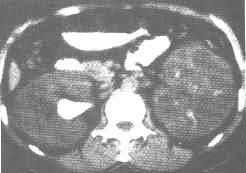

(7)CT顯示雙腎增大,外形呈分葉狀,有多數充滿液體的薄壁囊腫。